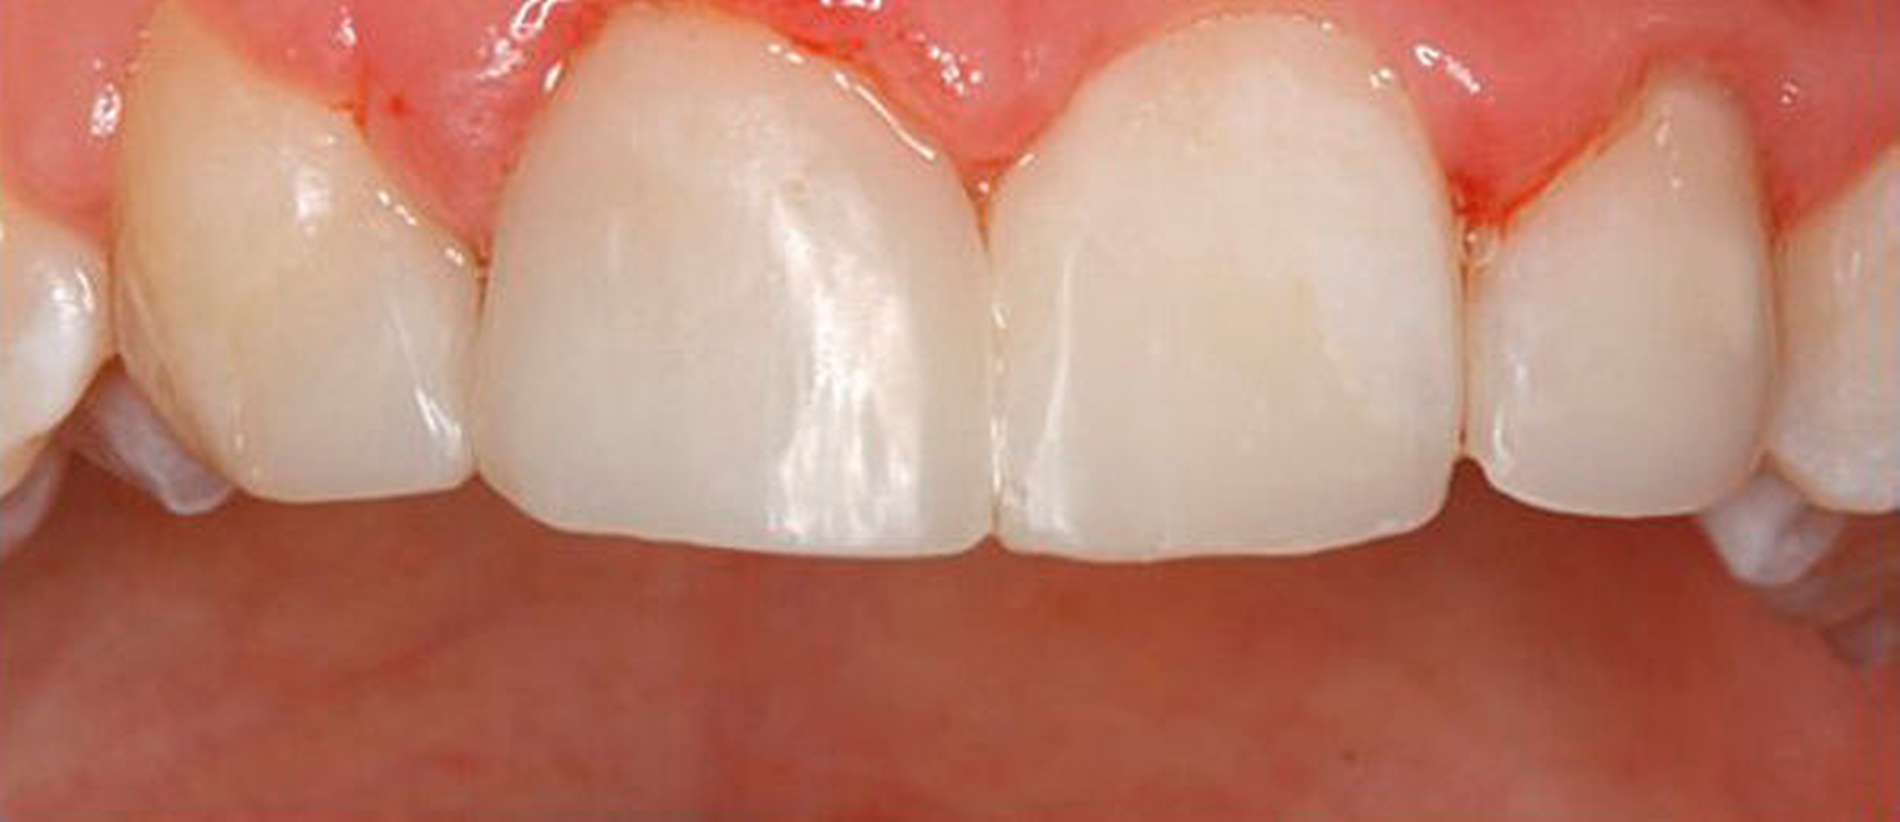

Die Rekonstruktion von Zähnen mit Komposit ermöglicht eine direkte und maximal zahnerhaltende Therapie, bei der die Zahnhartsubstanz nicht oder nur minimal im Sinne einer Anschrägung abgetragen werden muss. Im Vergleich zur Rekonstruktion mit keramischen Veneers muss dabei in der Regel wesentlich mehr Zahnhartsubstanz geopfert werden, um die nötigen Keramikschichtstärken einhalten zu können. Reparaturen, Farb- und Formanpassungen lassen sich mit der Komposittechnik im Vergleich zu Keramikrestaurationen immer wieder anpassen. Insbesondere bei jungen Patienten im Wachstum ist dies von Vorteil, um bei Veränderungen der Gingivaverhältnisse die rekonstruierten Zähne ihren Nachbarzähnen anzupassen (Verschluss schwarzer Dreiecke, zervikale Ausformungen).

In beiden Falldarstellungen wurden diese Bedingungen eingehalten. Eine Besonderheit stellt die Kombination von kieferorthopädischem Lückenschluss und Autotransplantation im zweiten Fall dar. Hier war vor der Rekonstruktion mittels Kompositaufbau eine Bewegung des Transplantats und der rechten Seitenzahnreihe erforderlich. Beides gestaltete sich ohne Probleme und sollte auch beim Verlust mehrerer Schneidezähne bedacht werden. Der Lückenschluss im Unterkiefer nach Keimentnahme konnte mithilfe skelettaler Verankerung ebenfalls reibungslos erfolgen. Es sollte jedoch wie beim kieferorthopädischen Lückenschluss die Anlage der dritten Molaren in der verkürzten Zahnreihe geprüft werden, um für den zweiten Molaren des Gegenkiefers einen Antagonisten zu haben. Ziel des Beitrags war es, die Autotransplantation nach Frontzahnverlust und Aplasie ins differenzialdiagnostische und -therapeutische Spektrum als gleichberechtigte Variante einzubeziehen.